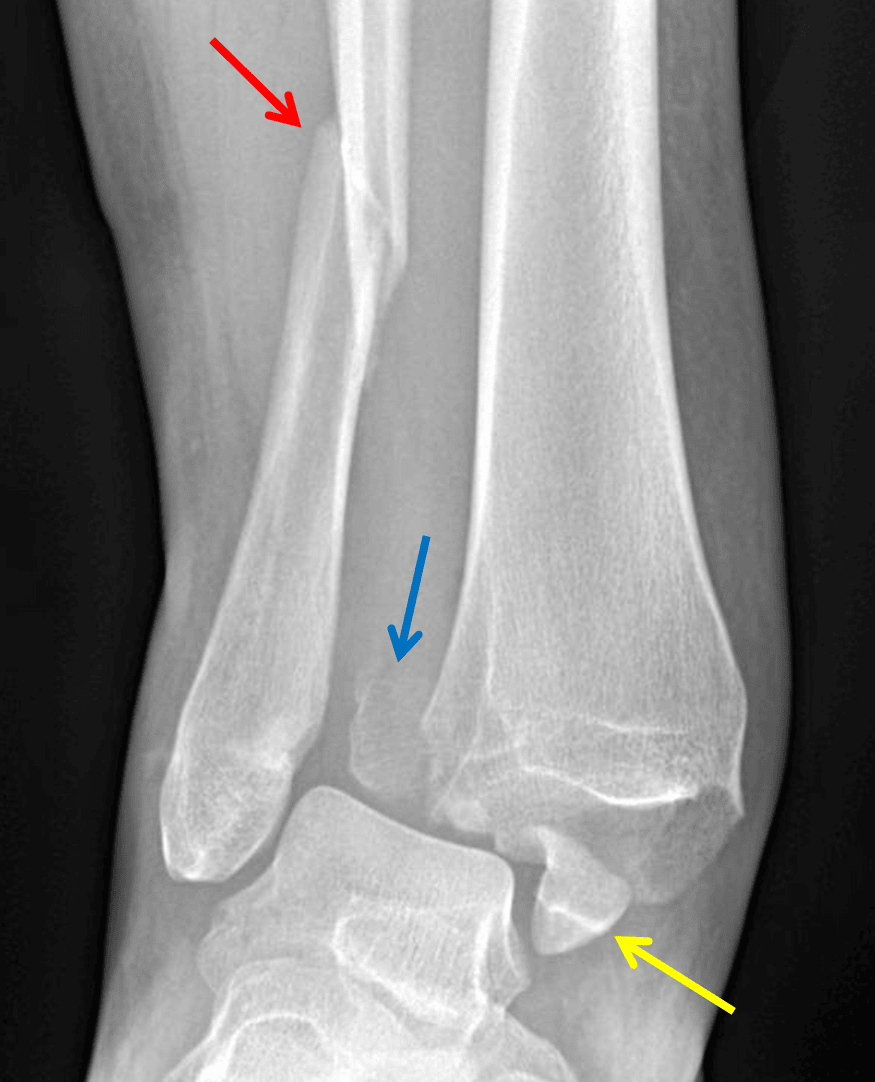

- Acute oblique fracture of the distal fibula with approximately 1 cm override and posterolateral angulation

- Acute distracted fracture of the medial malleolus with approximately 2 cm lateral displacement

- Acute mildly comminuted fracture of the posterior malleolus with approximately 2 cm lateral displacement

- Posterolateral dislocation of the tibiotalar joint

- Marked widening of the distal tibiofibular syndesmosis

Weber type C fracture - Angulated distal fibular fracture (red arrow) with associated tibiofibular syndesmotic injury and displaced posterior (blue arrow) and medial (yellow arrow) malleolar fractures.